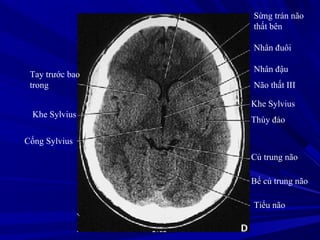

Sừng trán não

thất bên

Nhân đuôi

Nhân đậu

Não thất III

Khe Sylvius

Thùy đảo

Củ trung não

Bể củ trung não

Tiểu não

Tay trước bao

trong

Cống Sylvius